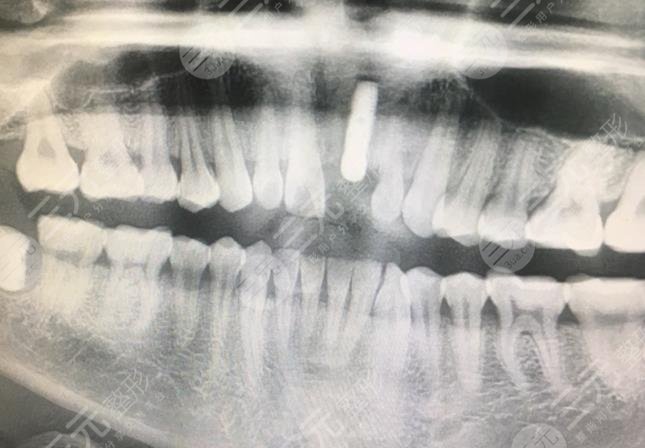

三、武汉德韩口腔医院种植牙案例分享

日常生活一些人因为牙齿缺少,迫不得已种植牙,但许多人并并不是很了解种植牙,感觉恐怖,其实不是,下边我共享一下做种植牙的整个过程吧因为一次意外导致一颗门牙掉了,因为各种各样原因,一直也没有去修复它,直至参与工作中了,突然感觉这颗牙太不利于个人整体形象了,有一次,原本老总要带我一起去参加一个关键商谈的,但之后突然又修改了想法,我了解到和这颗掉牙齿相关。

因此我就有了一定要做好这颗牙的的想法,可是考虑到价格会有点太贵了,因此没有做,如今我在一般的员工晋升到主管,因此交际也慢慢的大量,每日应对的人都许多,本身的形象确实更关键了,因此就取出了一些钱做了我之前不舍得做的种植牙。在朋友的提议下,我赶到了武汉德韩口腔医院开展牙齿种植。

正规种植牙的过程有点漫长,比一般的牙齿手术都长,它长达了2个多月,因为在种植了种植体后需要等它长好后才能进行后续的手术,其中重要的也就是种植体的按照了,然后就是基台和牙冠的按照了,整体手术还是很顺利的,果也较为的不错。

(点这里!在线免费咨询价格)手术后,我对着镜子照了照,确实象确实一样,用心看便是这颗刚种出去的牙好像比其他的牙齿略白一点点,但不显著。现如今种完牙也一个多月了,前几日去复诊了,医生说挺不错的,没有什么难题,挺高兴的。期待我的共享能帮助到一些想了解种植牙齿全部全过程的盆友哦。